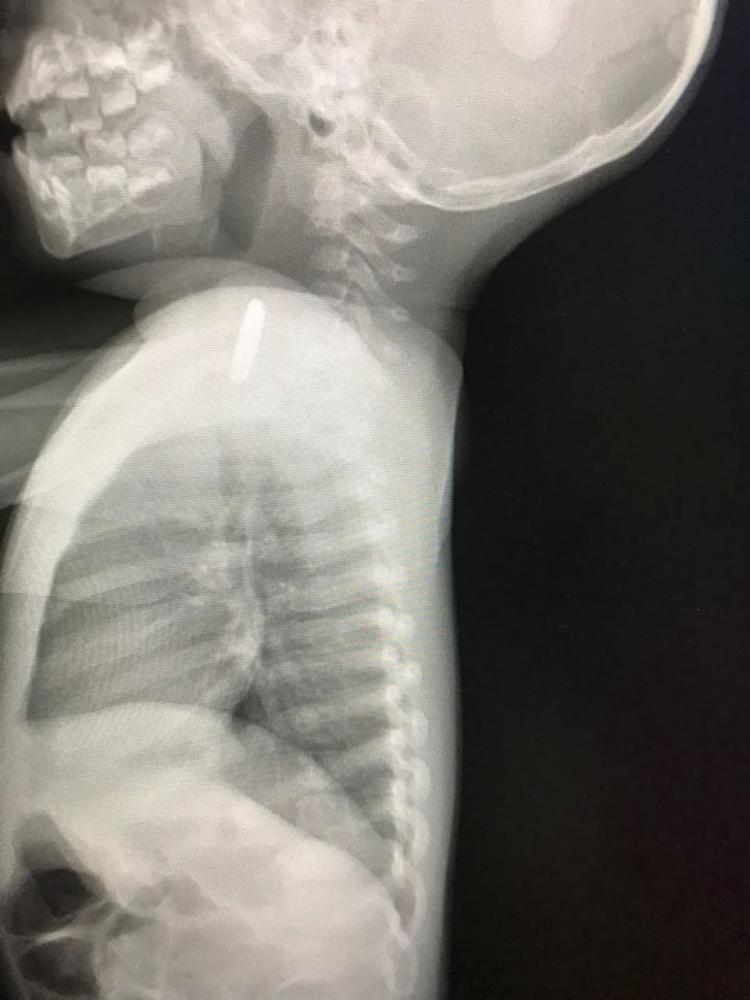

وكانت الطفلة عانت من آلام في الحلق، ونقلها ذووها إلى عدد من المرافق الصحية في القريات وخارجها، على مدى أسبوع كامل، دون التوصل إلى حل، وحين وصلت إلى مستشفى القريات العام أخضعت للفحوصات والأشعة التي أظهرت وجود جسم معدني أعلى المريء.

وأدخلت الطفلة إلى غرفة العمليات، وبالاستعانة بمنظار علوي، تبين ابتلاعها بطارية ساعة أدت إلى خروج بعض المحتويات الكيميائية منها وتسببت في التهاب المريء.